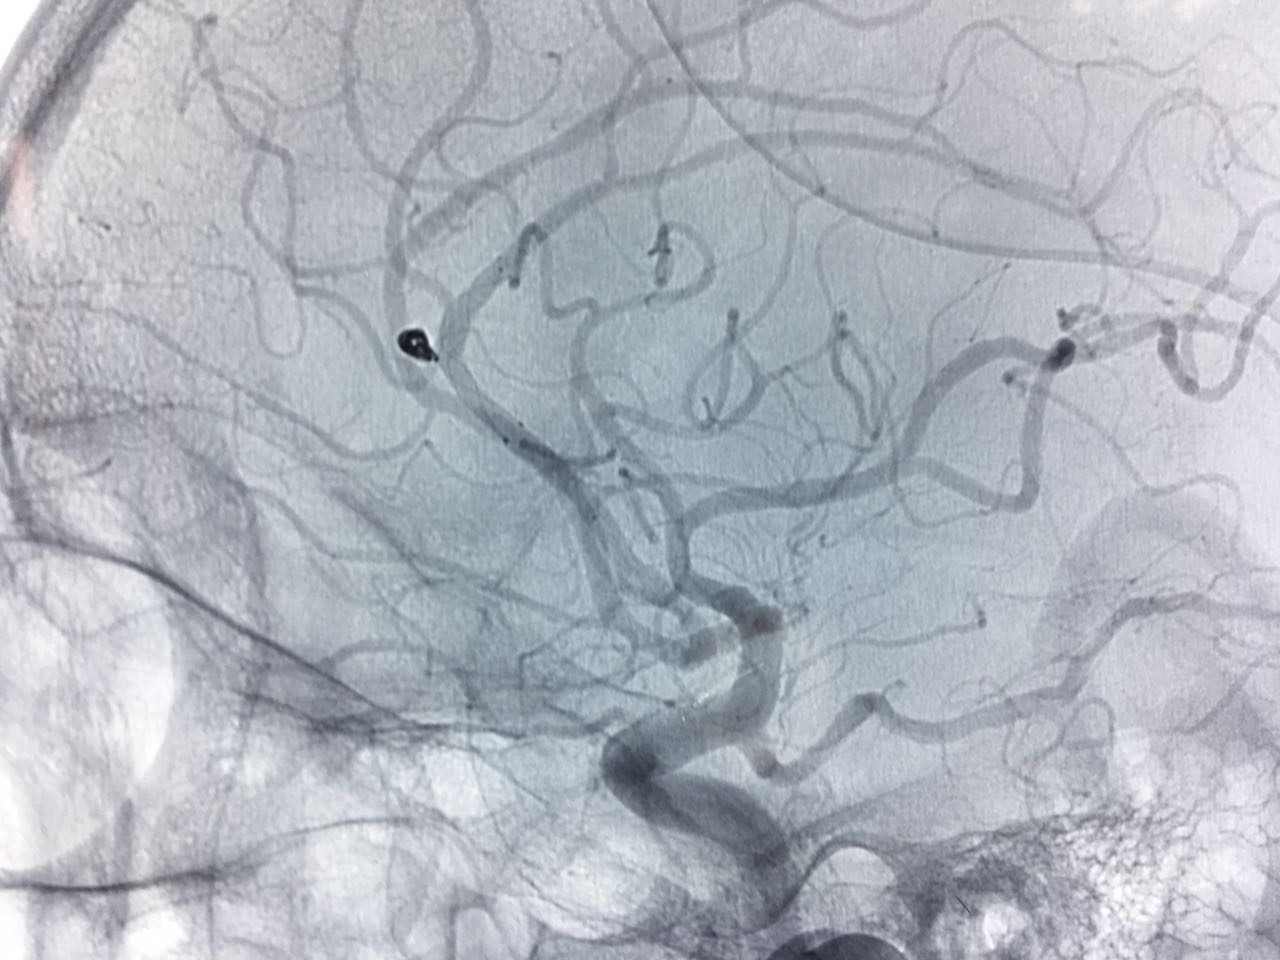

患者王某某,因“突发头痛2小时”来我院就诊,入院后急查颅脑CT示蛛网膜下腔出血。高磊主任急查房并阅片,考虑病人出血部位以双侧外侧裂、皮层下沟池为主,左侧为主,病人四叠体池、桥池、环池周围血量很少,为次级血管动脉瘤可能性较大。遂行颅脑MRA检查初步筛查,未见动脉瘤。考虑病人急性期血管痉挛,仍应继续排查动脉瘤,2天后为其行全脑血管造影术,造影示:胼缘动脉与大脑前动脉交界处动脉瘤。胼缘动脉与大脑前动脉交界处动脉瘤在临床上极其少见,手术风险极大,此前此类病人只能开颅动脉瘤手术夹闭,创伤大、预后差、并发症多。高主任组织科室技术骨干积极进行术前讨论,最终决定为患者实施全身麻醉+支架辅助下动脉瘤微弹簧圈栓塞术。手术顺利完成,术后患者恢复良好。